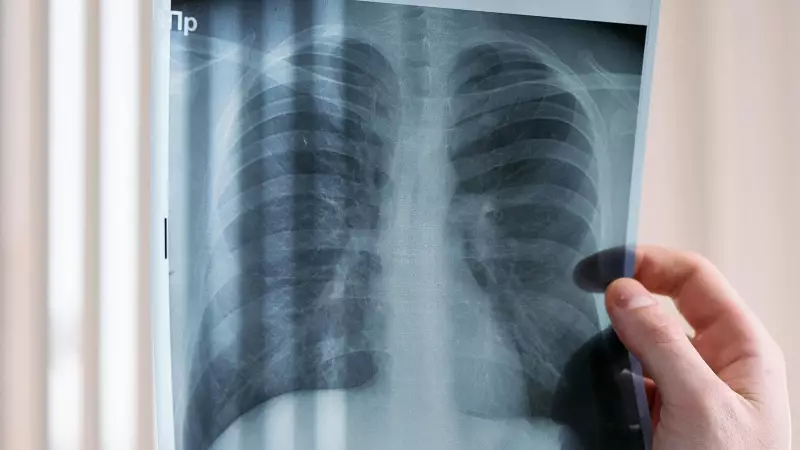

The patient, who maintained an active lifestyle and had no family history of cancer, initially dismissed her persistent cough and breathing difficulties as seasonal allergies. However, when her symptoms worsened over several months, medical investigations revealed the shocking truth: advanced stage lung cancer.

Medical professionals are now calling this phenomenon the "breathers disease" – lung cancer affecting people who don't smoke but are exposed to dangerous levels of air pollution. "We're seeing a disturbing trend where perfectly healthy non-smokers, particularly women, are developing lung cancer," explained the treating physician.